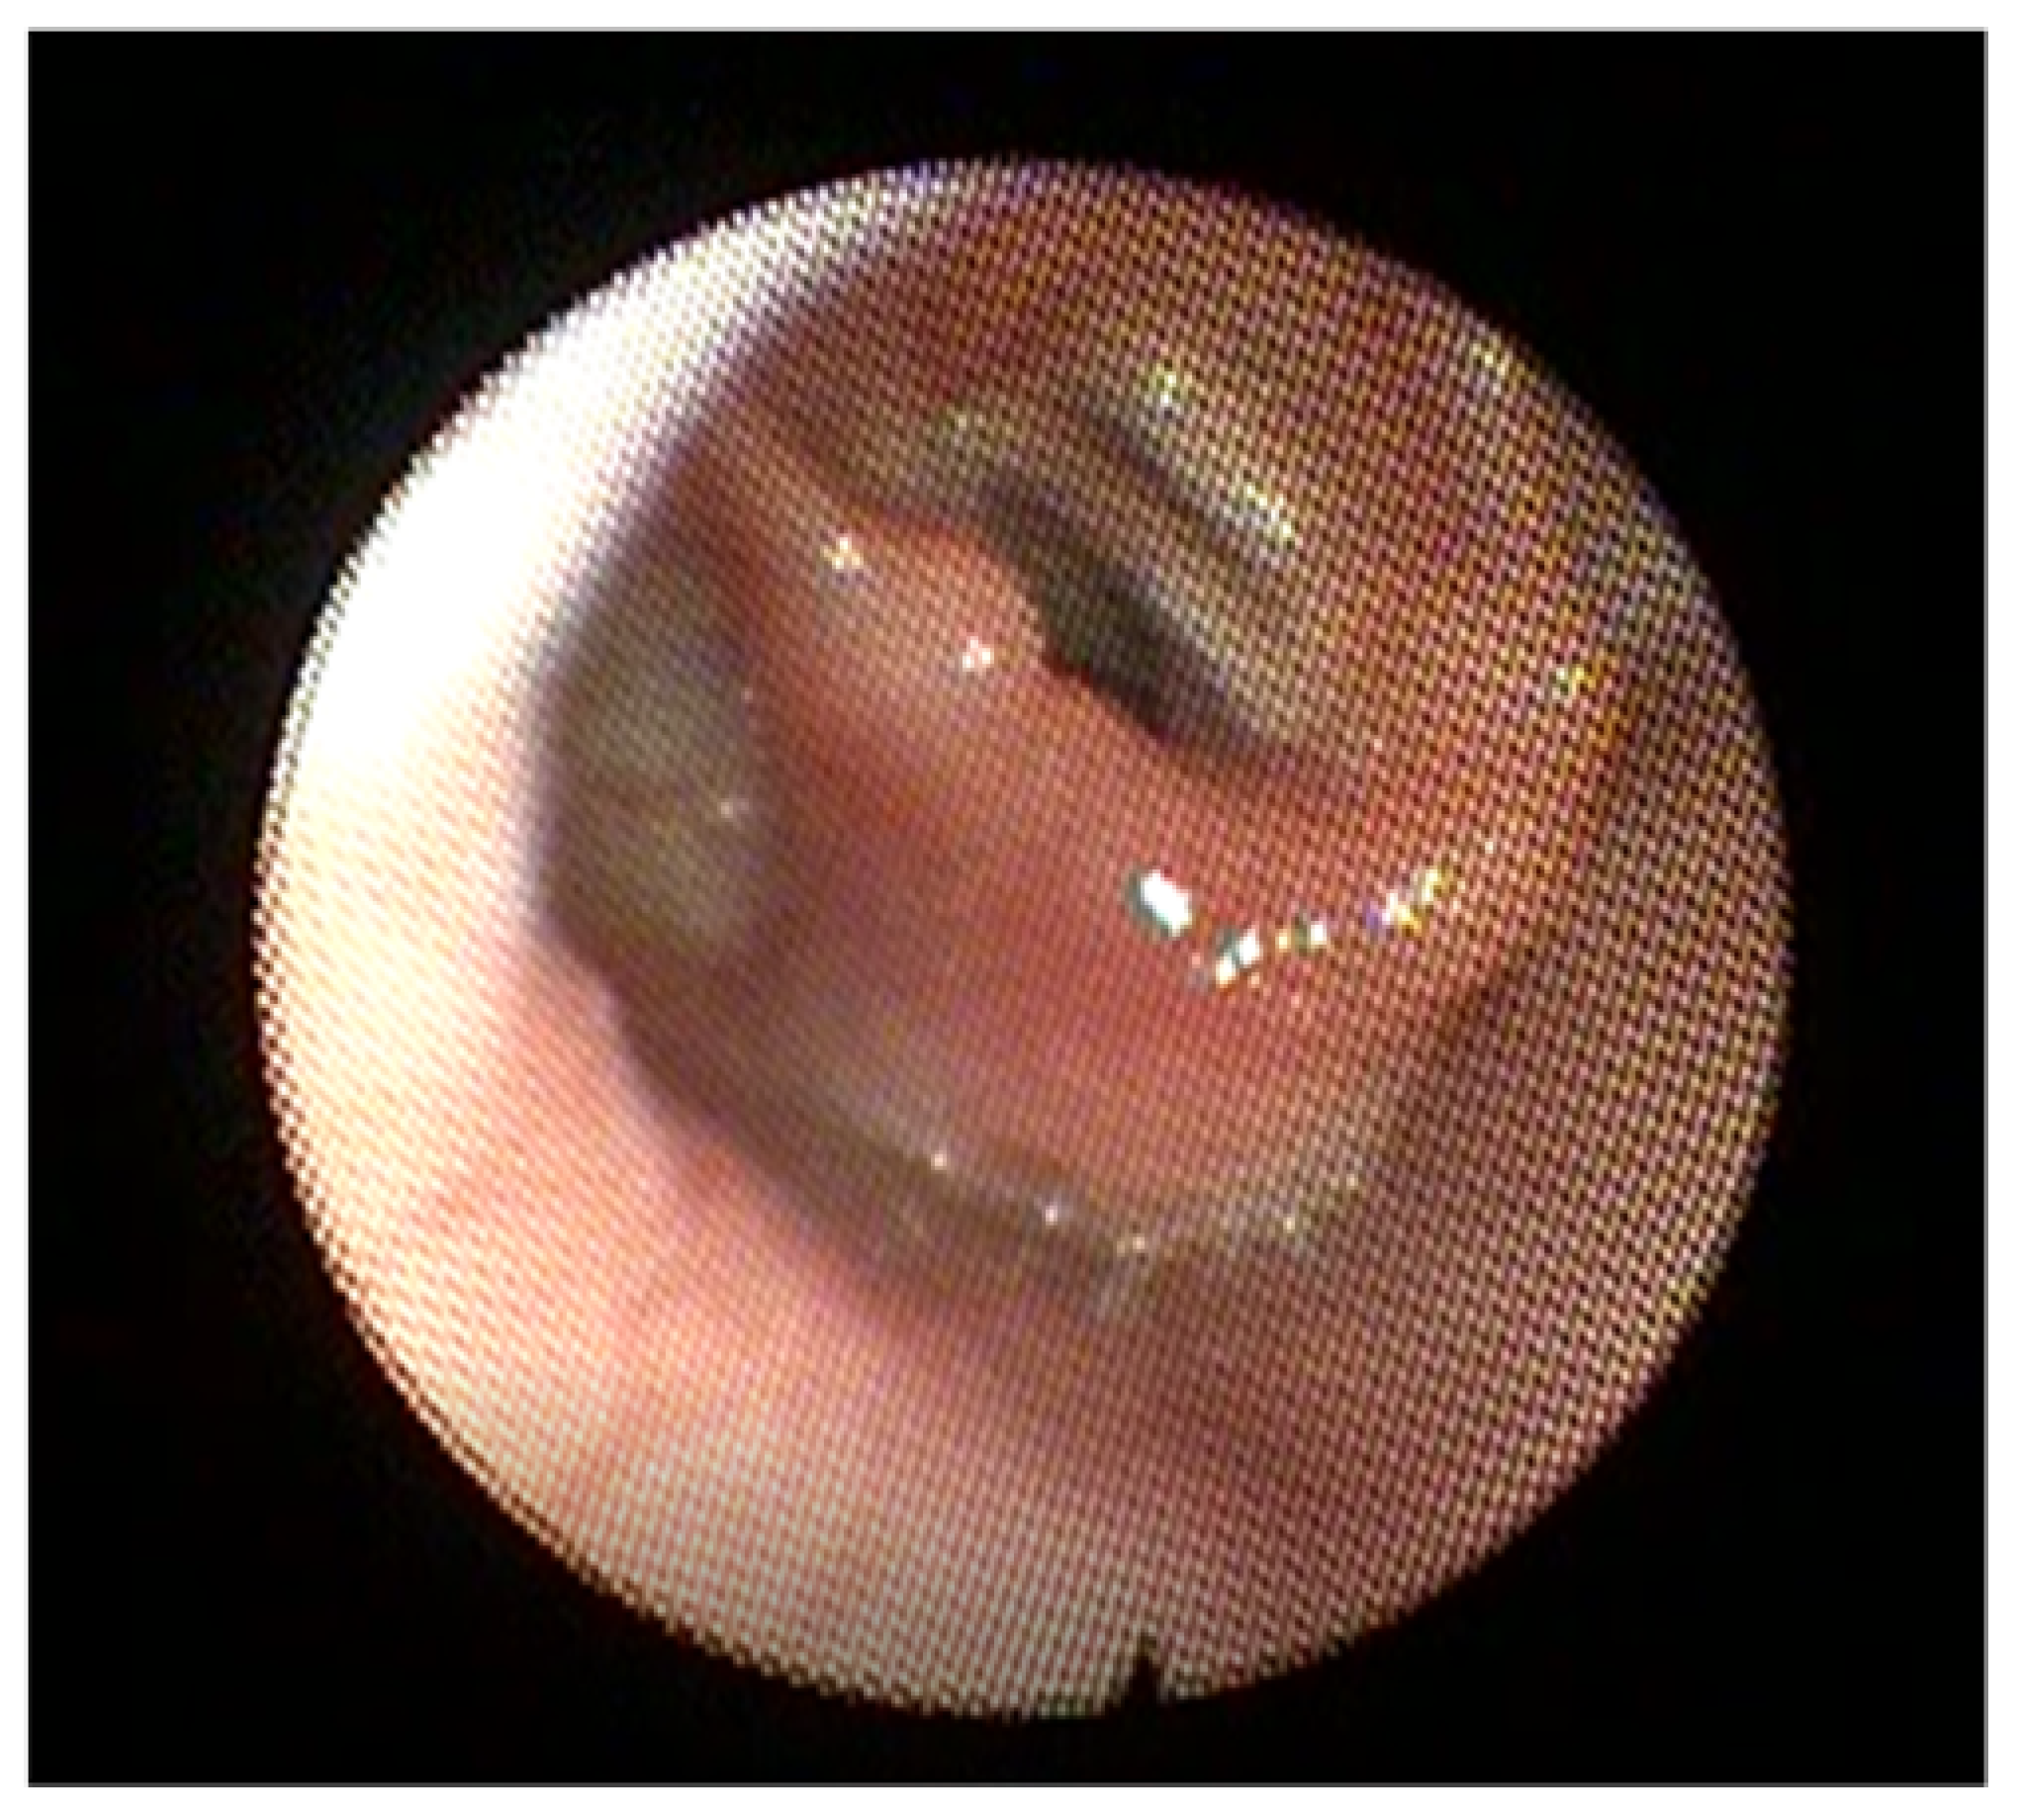

2.2. Vocal Cord Paralysis